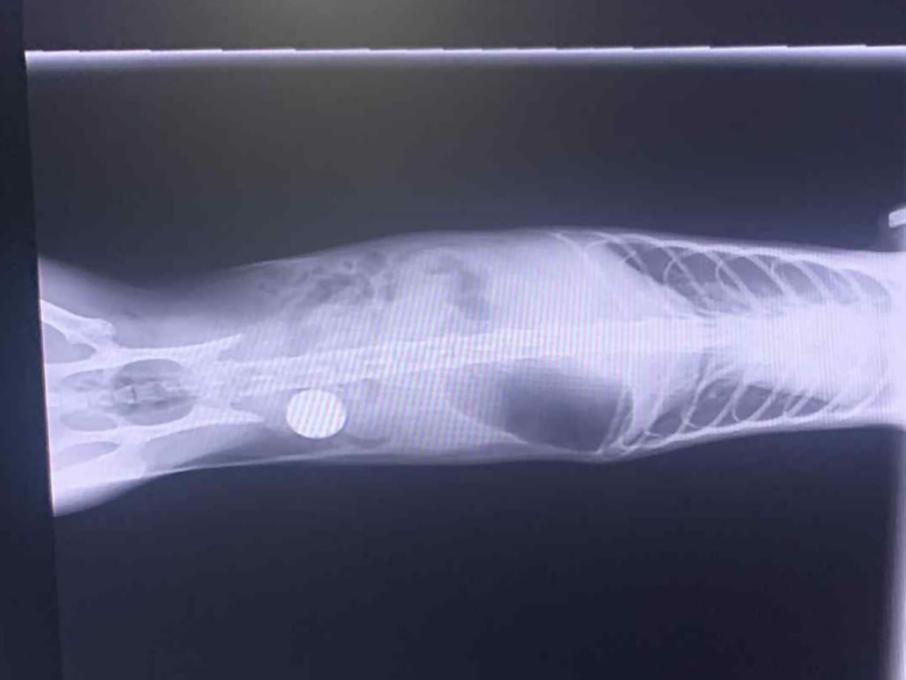

Функциональность учреждения позволяет закрывать самые разнообразные запросы: от рутинной «профилактики счастливой жизни» — вакцинации, чипирования и консультаций по уходу — до сложных хирургических операций и длительного терапевтического сопровождения. Благодаря точной диагностике, включающей УЗИ и лабораторные исследования, врачи ПроВет доходят до сути проблемы, избегая лишних назначений и сосредотачиваясь на результате. Особое внимание уделяется стоматологии и хирургии мягких тканей, где безопасность анестезии и быстрая реабилитация являются золотым стандартом.